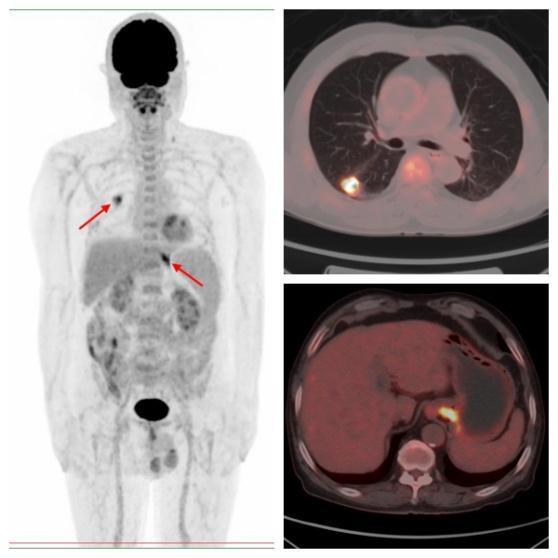

图片

病例2,PET/CT示左肺下叶、直肠代谢异常,符合双原发癌;之后患者行支气管镜下活检,病理证实原发肺鳞癌;行肠镜下活检,病理证实为原发直肠溃疡型腺癌。